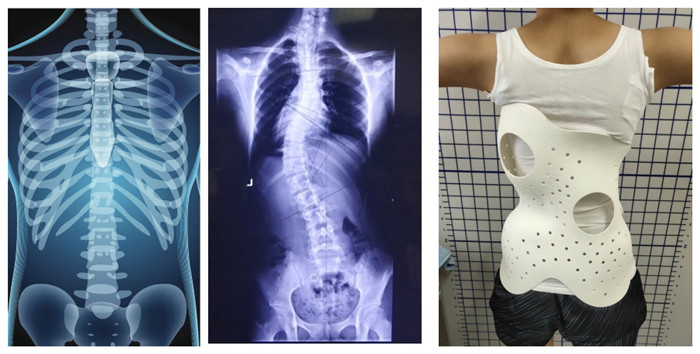

A scoliosis spine needs to corrected, then a orthoses is required. We choose SLS 3D printing to print a customized orthoses which has a lattice structures to reduce weight dramatically, and it can enhance breath ability with good efficacy, comfortable and grace design.

X-ray imaging → 3d scanning → design & 3d modeling → 3d printing → 3d printing scoliosis orthoses.

Compared with the traditional manufacturing technology, SLS 3D printing greatly improves the production efficiency and shortens the production time. It is much more comfortable than traditional orthoses.

A Normal Spine A Scoliosis Spine Scoliosis Orthoses